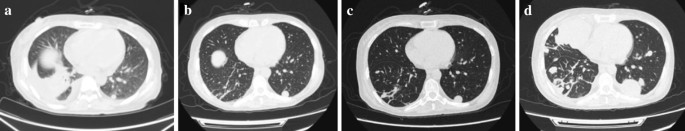

The diameter of the left lung metastases increased from 0.7 cm at baseline to 1.5 cm during radiotherapy, and showed no changes after completion of radiotherapy (Fig. 2a–c). After 14th days of radiotherapy, the patient was treated with the second and third doses of nivolumab (3 mg/kg every 2 weeks). Eighteen days after administration of the third dose of nivolumab, the patient’s general condition deteriorated; this was associated with an immune-related adverse event, namely, inflammatory arthritis, which presented as severe pain and deformed joints in the hands and knees (Fig. 3). Computed tomography scans of the right kidney lesions showed almost no change during treatment (Fig. 4a, b), but the diameter of the left lung metastases sharply increased to 4.9 (Fig. 2d). Moreover, the absolute count of peripheral lymphocytes decreased from 2.75 × 109/L to 0.74 × 109/L after radiotherapy.

Radiological evaluation alone is not enough to distinguish pseudoprogression from HPD, so a biopsy of the lung metastasis was performed. It showed no infiltration of lymphocytes (Fig. 5 and Additional file 1: Fig. S1); thus, pseudoprogression was excluded. Subsequently, the patient received prednisone therapy. However, her general condition worsened and she received supportive care. She died of respiratory failure on the 70th day after administration of the third dose of nivolumab.